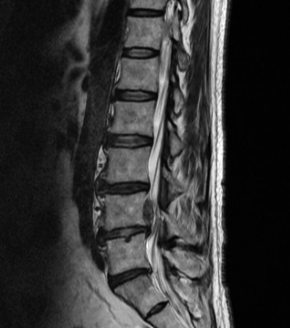

허리디스크 증상 치료방법 및 수술비용에 대해 알아보겠습니다. 허리디스크는 척추 뼈 사이에 있는 디스크가 손상되어 신경을 압박하는 질환입니다. 디스크는 척추뼈 사이의 충격을 흡수하고 척추의 움직임을 부드럽게 해주는 역할을 하는데, 이 디스크가 손상되면 신경을 압박하여 통증, 마비, 감각 이상 등의 증상이 나타납니다. 허리디스크는 흔히 40~50대 중년층에서 발생하지만, 젊은 나이에도 발생할 수 있습니다.

허리디스크의 치료방법은 증상의 심각성과 개인의 상황에 따라 다르게 선택됩니다. 일반적으로는 비수술적 치료가 우선적으로 시도되며, 수술적 치료는 보존적 치료로 증상이 호전되지 않거나 신경마비가 있는 경우에 고려됩니다.

허리디스크는 정확한 진단에 따라 올바른 치료 방법을 선택해야 합니다. 의사와 상의하여 자신에게 가장 적합한 치료 방법을 결정하시